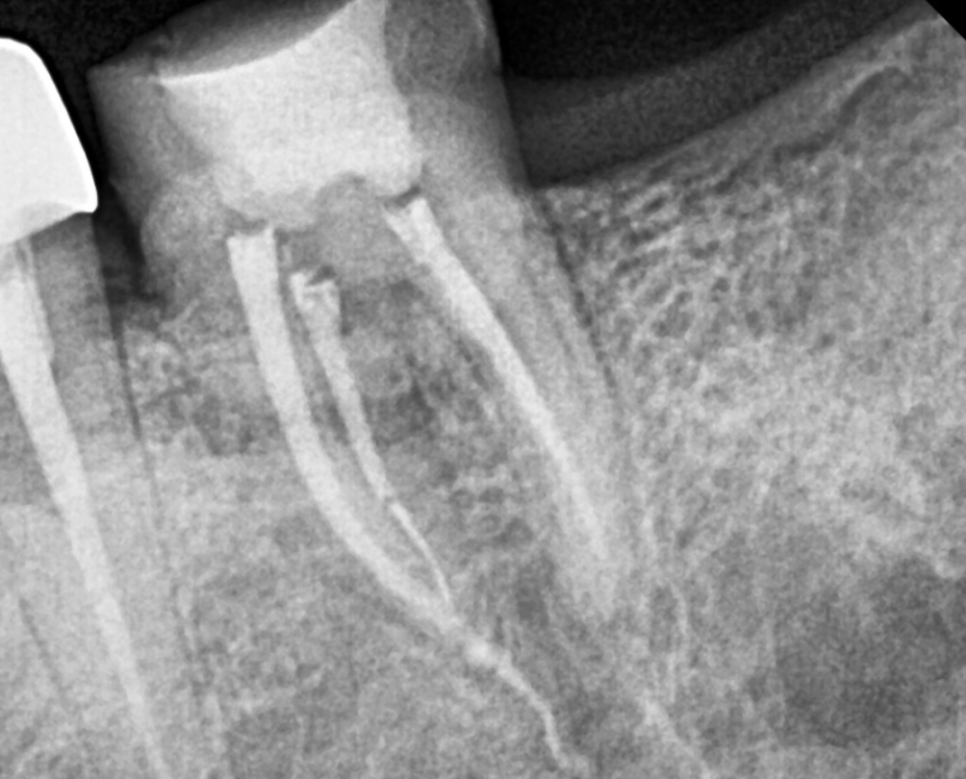

251010 신경치료가 마무리된 모습